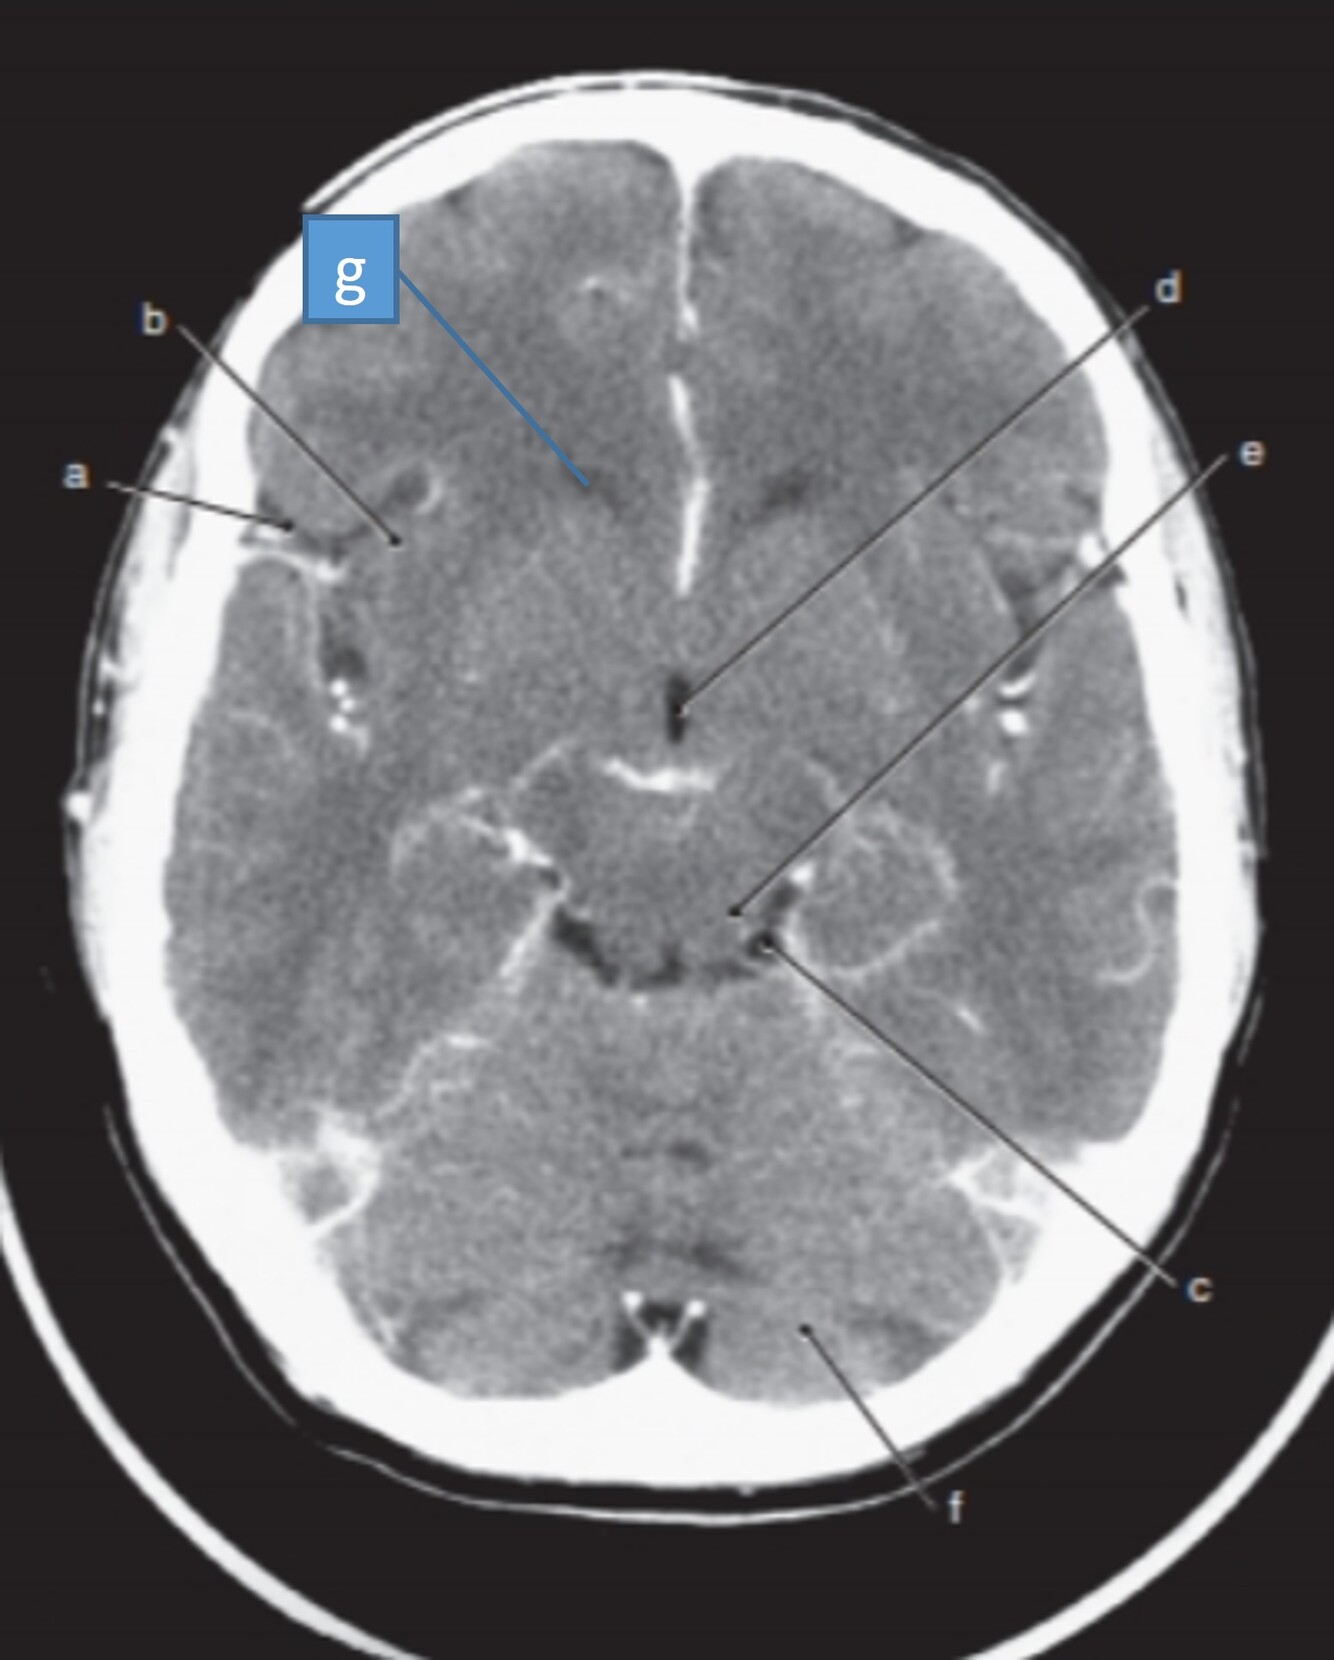

Label a,b,c,d,f,g

A

a-Rt lateral fissure

b=Insula

c=Quadrigeminal cistern

d-3rd ventricle

f-Cerebellum

g=Anterior horn (of rt lateral ventricle)